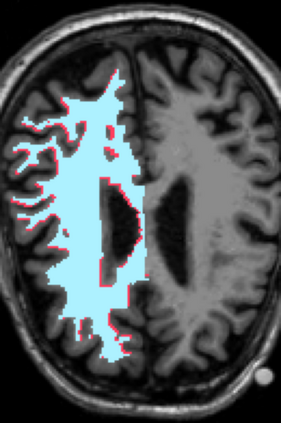

Deep neural networks for medical image reconstruction are traditionally trained using high-quality ground-truth images as training targets. Recent work onNoise2Noise (N2N) has shown the potential of using multiple noisy measurements of the same object as an alternative to having a ground truth. However, existing N2N-based methods cannot exploit information from various motion states, limiting their ability to learn on moving objects. This paper addresses this issue by proposing a novel motion-compensated deep image reconstruction (MoDIR) method that can use information from several unregistered and noisy measurements for training. MoDIR deals with object motion by including a deep registration module jointly trained with the deep reconstruction network without any ground-truth supervision. We validate MoDIR on both simulated and experimentally collected magnetic resonance imaging (MRI) data and show that it significantly improves imaging quality.